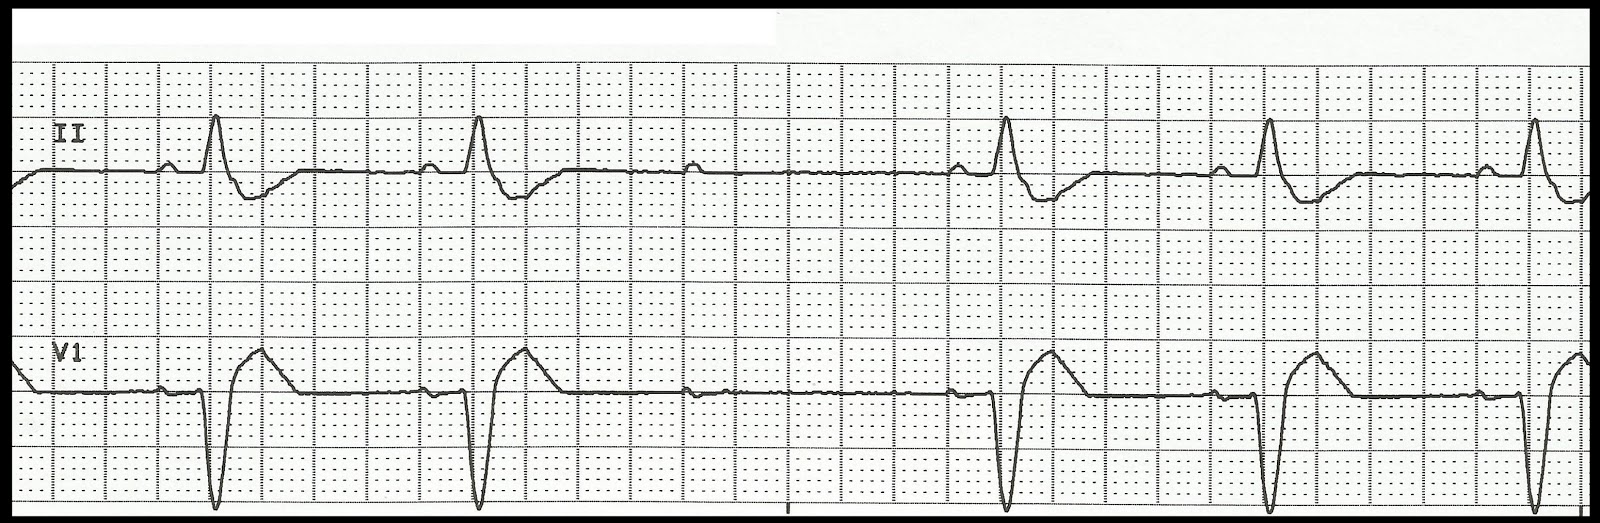

01. Atrial fibrillation